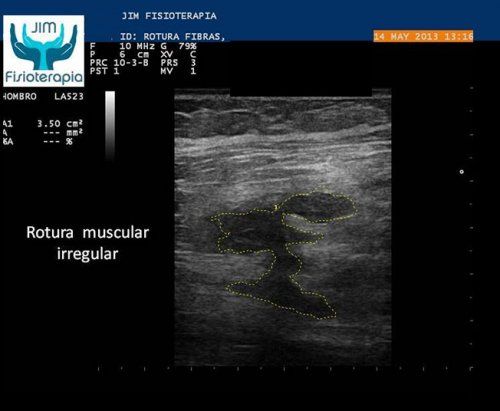

Tratamiento de rotura muscular mediante EPI® en Madrid

Varón de 47 años, sufre una rotura muscular en el bíceps femoral de la pierna derecha al realizar una brusca contracción excéntrica asociada a movimiento de torsión, al evitar la caída de su motocicleta.[...]